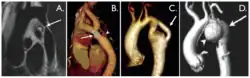

Coarctation of the aorta can be accurately diagnosed with magnetic resonance angiography. In teenagers and adults echocardiograms may not be conclusive.

The severity of coarctation of the aorta can be rated by a combination of the smallest aortic cross-sectional area of the aorta (adjusted for body surface area) as measured by 3D-rendered contrast MRI, as well as mean heart rate–corrected flow deceleration in the descending aorta as measured by phase contrast magnetic resonance imaging.[9]

Aortic coarctation using different imaging techniques[10] -

Coarctation of the aorta -

Coarctation of the aorta